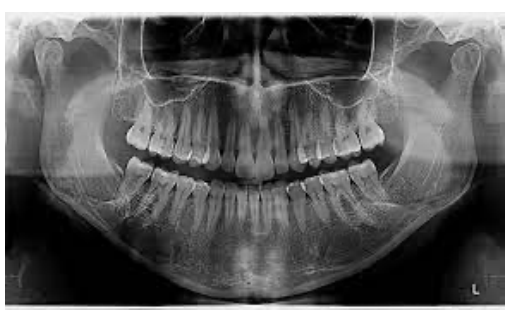

Uma mulher de 81 anos de idade, hipertensa, diabética, dislipidêmica e com disfunção temporomandibular, em uso de enalapril, hidroclorotiazida, metformina, atorvastatina e, recentemente, duloxetina, por queixa de choro fácil e pouca vontade de realizar as atividades, com o alto cuidado piorando aos poucos, foi ao serviço de emergência com quadro de importante dificuldade de abertura da boca há dois dias, associado à forte dor local, sem outros achados associados e negando ativamente outros sintomas. Ao exame físico: lúcida; pouco colaborativa com o exame físico; abertura da boca limitada, com crepitação de região de ATM; FC de 67 bpm; FR de 17 ipm, tax. 36,1⁰; e MV presente, bilateralmente, sem ruídos adventícios.

Com base nesse caso hipotético, assinale a alternativa que apresenta a conduta mais adequada no momento.